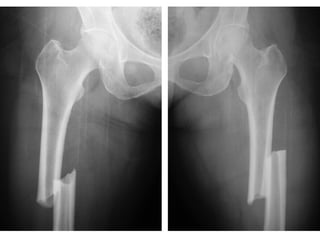

Femoral Fracture

• Femoral fractures in a multiply injured patient are not

automatically treated with intramedullary nailing because :

- ‘second hit’

- fat emboli

• Patients with a chest injury are most prone to deterioration

after an intramedullary nailing procedure

• Bilateral femoral fracture is associated with a higher

mortality rate and incidence of adult respiratory distress

syndrome than is a unilateral femoral fracture

• Increase in mortality may be more closely related to

associated injuries and physiologic parameters than to the

bilateral femoral fracture itself

Femoral Fracture • Femoralfractures in a multiply injured patient are not automatically treated with intramedullary nailing because : - ‘second hit’ - fat emboli • Patients with a chest injury are most prone to deterioration after an intramedullary nailing procedure • Bilateral femoral fracture is associated with a higher mortality rate and incidence of adult respiratory distress syndrome than is a unilateral femoral fracture • Increase in mortality may be more closely related to associated injuries and physiologic parameters than to the bilateral femoral fracture itself